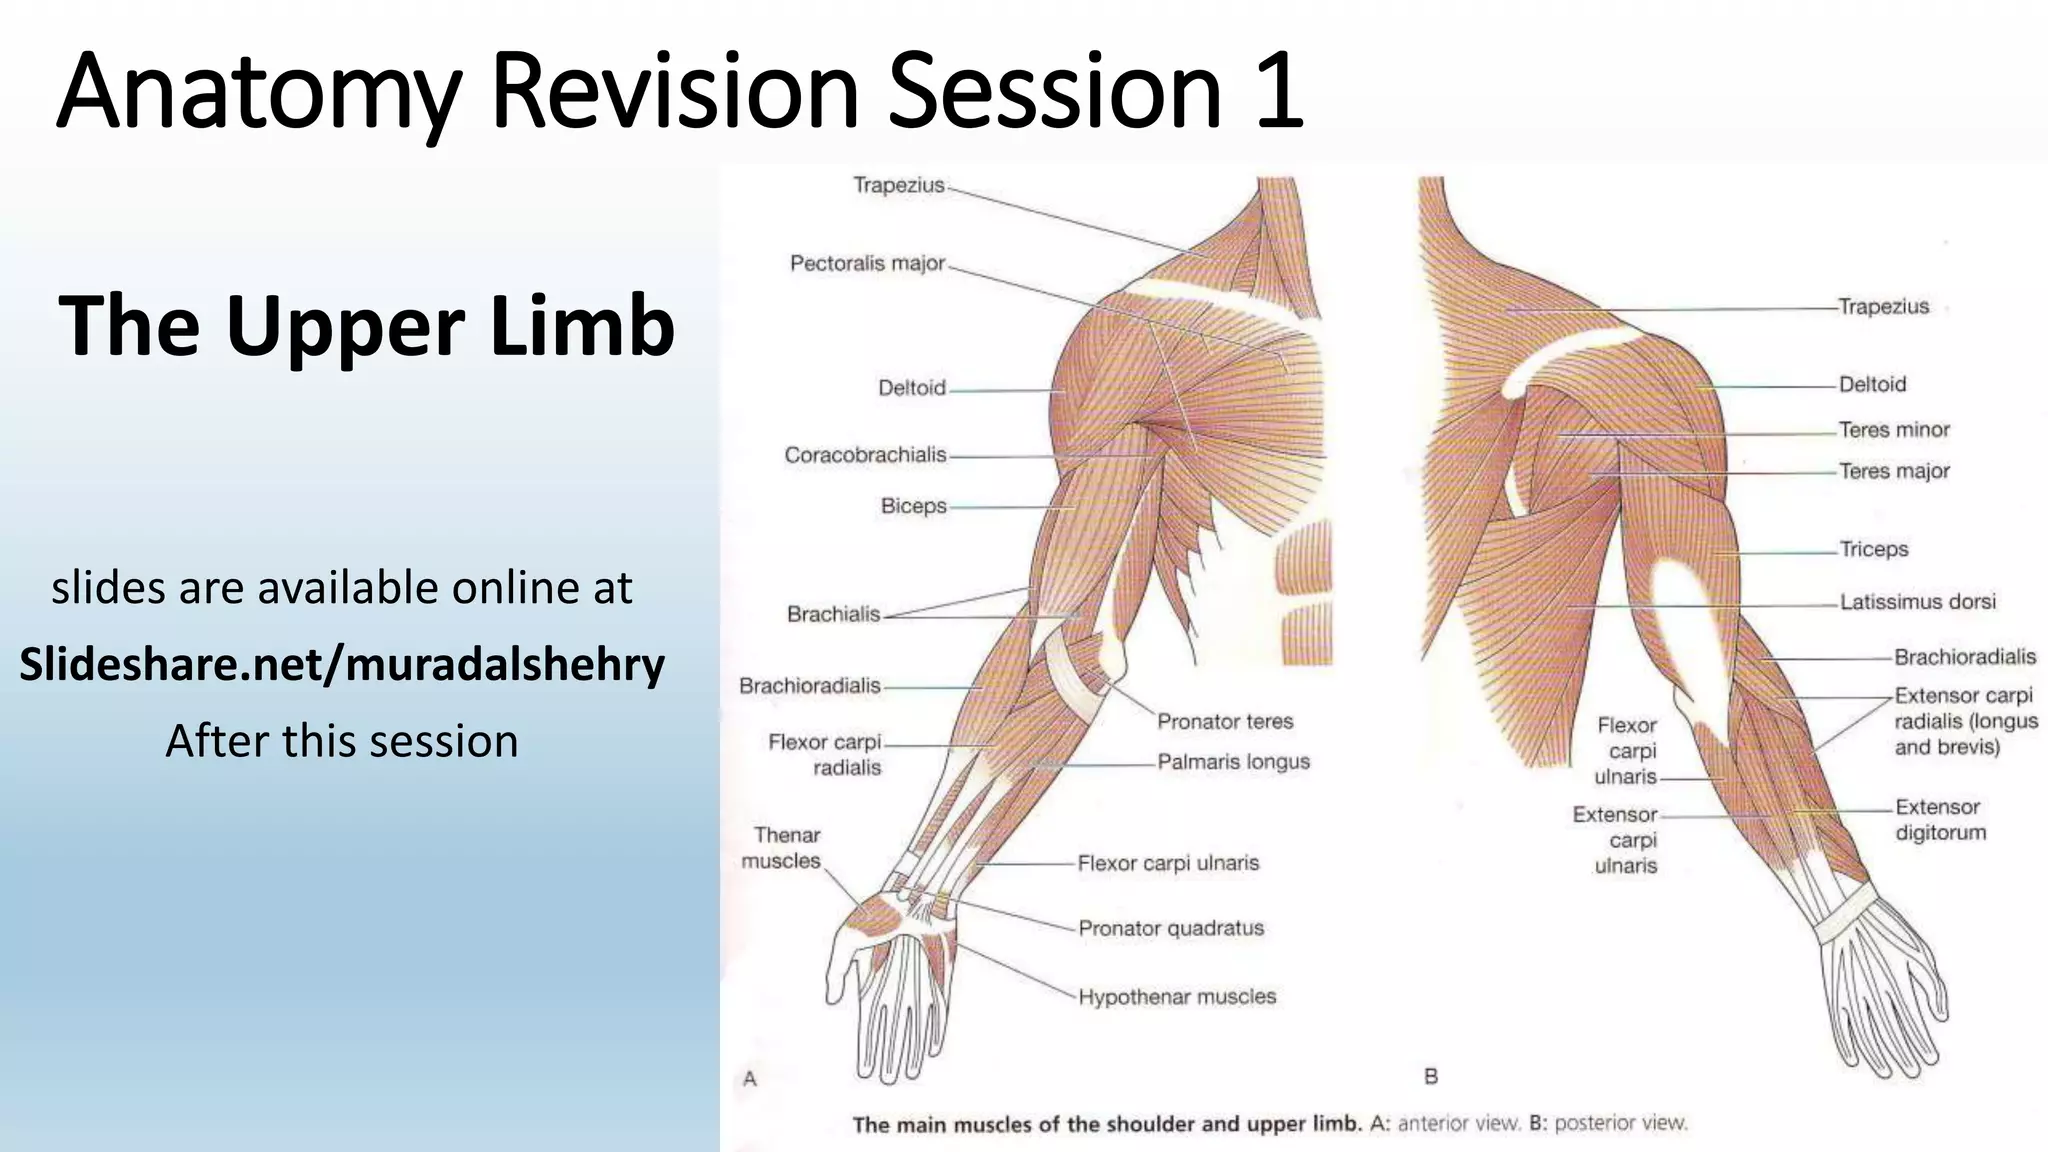

The document summarizes an anatomy revision session on the upper limb. It discusses various muscles of the upper limb including their origins, insertions, innervations and functions. Key muscles covered include the pectoralis major and minor, serratus anterior, deltoid, biceps brachii, brachialis, coracobrachialis, and triceps. It also discusses the rotator cuff muscles and muscles of the forearm including flexor carpi ulnaris and radialis. The session aims to help students identify upper limb muscles and understand their relations to nerves.